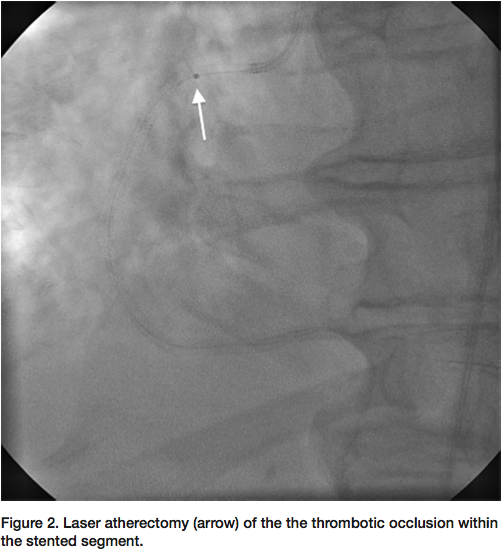

segment revealed an under-expanded stent with a reference vessel size of 4 mm. An NC Sprinter 4.0 mm balloon (Medtronic) was used to further dilate the stented segment, but with no improvement in flow. A ClearWay 1.0 x 10 mm perfusion balloon (Atrium) was then used to deliver intracoronary nitroglycerin, adenosine, and eptifibatide (Figure 3), with still no distal flow. Finally, the ClearWay balloon was used to deliver intracoronary tPA (2 mg bolus) with significant improvement in flow after 5 minutes of dwell time. Final angiogram revealed brisk TIMI-3 flow through the stented segment with excellent angiographic result (Figure 4).